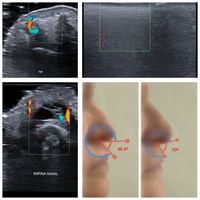

RINOMODELACIÓN ECOGRÁFICA

¿Corrige cualquier defecto nasal? Podemos corregir visualmente determinados aspectos estéticos de la nariz, como lam excesiva proyección del dorso de la nariz, punta nasal descendida, curvaturas o concavidades en el perfil nasal, y algunas asimetrías. Permite corregir visualmente determinados aspectos estéticos de la nariz. No se utiliza cirugía, sino infiltración de determinados productos de relleno. Entre los beneficios están corregir el dorso de la nariz, elevar discretamente la punta nasal o algunas asimetrías. Sin postoperatorios dolorosos o incapacitantes. Con la máxima seguridad que ofrece el mapeo previo que realizo con ecografía cutánea, que consiste en estudiar la anatomía nasal particular de cada paciente para poder hacer una inyección estética eficaz y más segura. Resultados inmediatos, y sin procesos dolorosos y prolongados de recuperación. De hecho los resultados estéticos son inmediatos.

Tiene algún tipo de riesgo? En general la nariz es un área compleja de infiltrar y hacerlo sin un análisis previo puede conllevar riesgos; pero con la información que nos da el estudio ecográfico previo que realizamos a todo paciente de rinomodelación, conocemos la anatomía nasal particular de cada paciente (vasos sanguíneos, capas a infiltrar/no infiltrar, etc) y eso permite hacer el tratamiento de la forma más eficaz y más segura posible. Resultados inmediatos, y sin procesos dolorosos y prolongados de recuperación. De hecho permite la reincorporación inmediata a la vida normal, con unos mínimos cuidados y por lo general sin molestias.